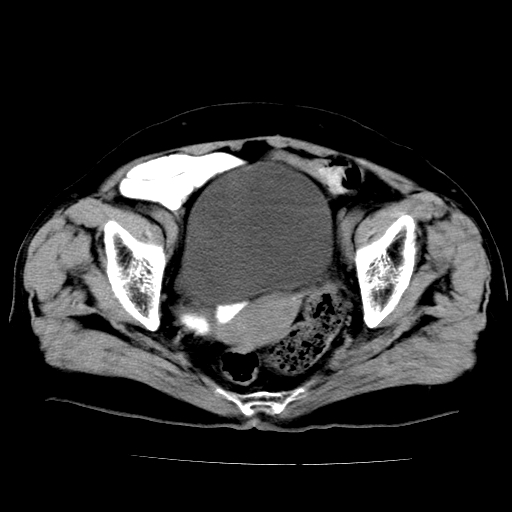

女,73岁,阴道流血一周。

宫颈不规则增大;结合临床考虑宫颈癌。建议作mri检查

1\\老年妇女突发阴道流血,常见病考虑宫颈癌.本病例宫颈部显示形态不规则,密度欠均匀,支持考虑宫 颈癌,建议mri 或阴道超声坚持

2\\但是盆腔两侧尚未见到明显肿大淋巴结等转移征象

宫颈不规则增大,左后方可见结节状突起.支持宫颈癌.

宫颈壁明显增厚,左侧为甚,宫颈癌待排,建议宫颈涂片细胞学检查。

宫颈不规则增大,周围脂肪间隙毛糙,结合临床考虑宫颈癌,盆腔内未见肿大淋巴结。